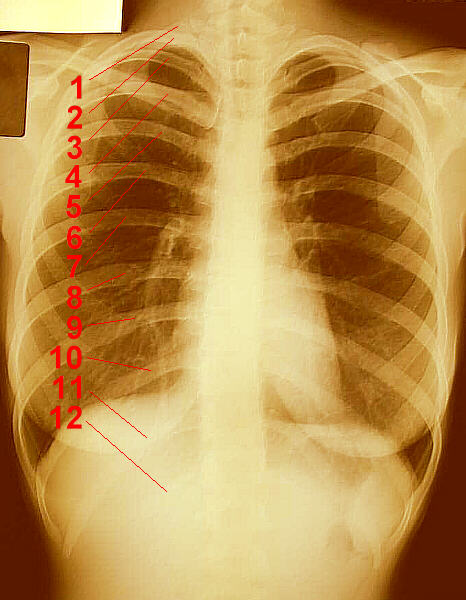

Over the last few years, I have received several e-mail message asking if the number of ribs is different in men and women. To correctly respond to these inquiries, I have researched this issue by looking up this information in several Anatomy and Physiology textbooks. All agree that, based on medical research (somebody actually dissected cadavers and counted ribs, somebody actually looked at x-rays and counted ribs), men and women have the same number of ribs as each other. For example, one book says:

Twelve pairs of flexible, archlike ribs form the lateral portions of the thoracic cage. They increase in length from the first to the seventh and then decrease again from the eighth to the twelfth.

Click on each of these photographs for a larger view.

Female Ribs Male Ribs Male Ribs

X-Ray of Female Ribs X-Ray of Male Ribs Male Skeleton

Unlike people in the Middle Ages, we do science these days (most of the time). We don’t just guess at how many teeth horses have or how many ribs people have. We get in there and count them, and then we know: both men and women have twelve pairs of ribs.